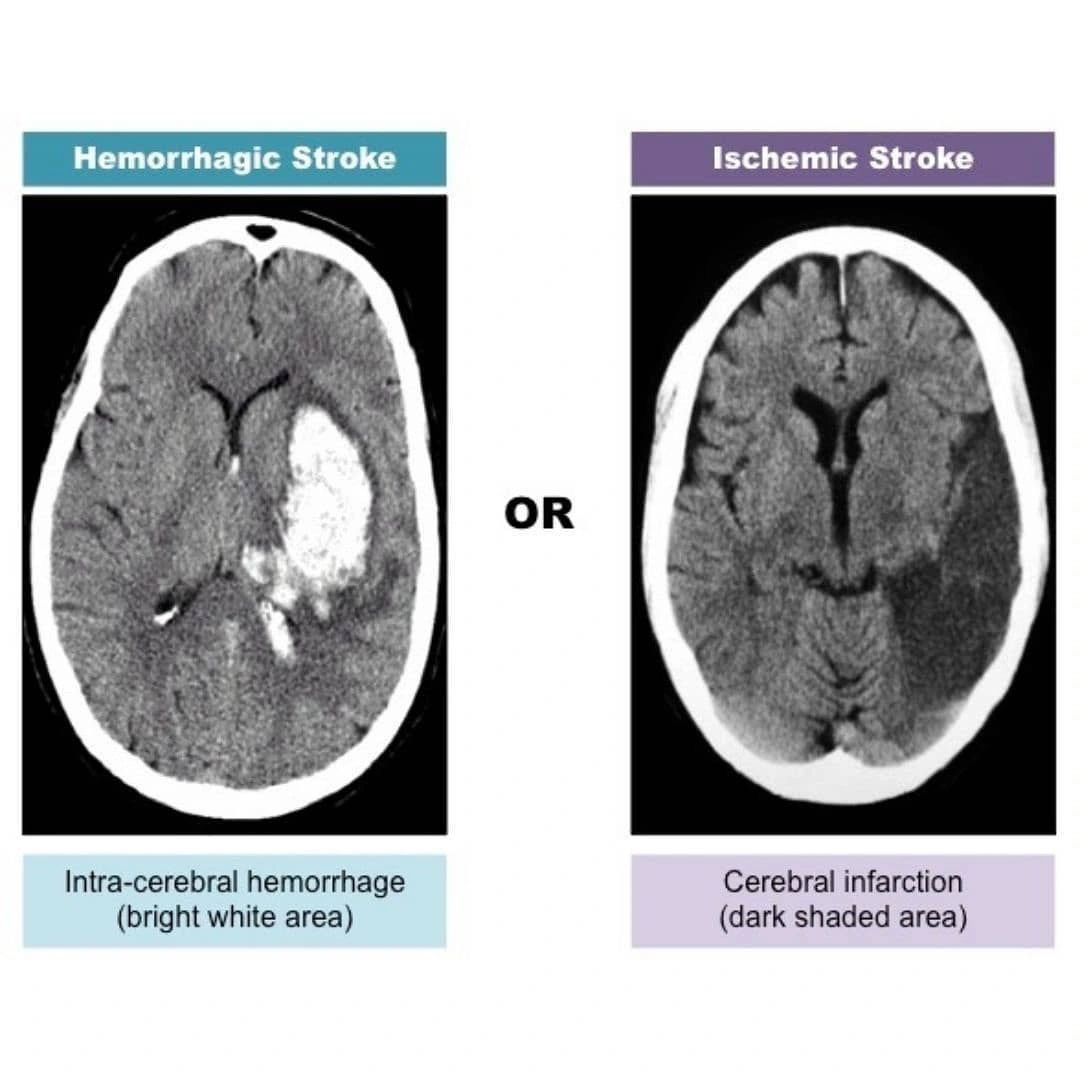

STROKE — THE BIG PICTURE

Ischemic Stroke (≈85%)

Cause: Arterial occlusion → cerebral infarction

Early CT (may be normal):

• Loss of gray–white matter differentiation

• Insular ribbon sign

• Hyperdense MCA sign

Late CT:

• Hypodense wedge-shaped infarct

• Sulcal effacement

• Mass effect due to edema

Rule: Always exclude hemorrhage on CT before thrombolysis.

Hemorrhagic Stroke (≈15%)

Cause: Vessel rupture → bleeding

CT hallmark:

• Hyperdense (white) blood

ONE-LINE MEMORY AID

CT Rules to Remember:

Blood = White

Ischemia = Dark (late)